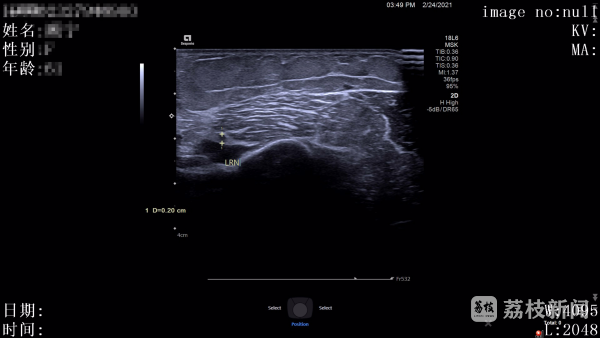

这个“非手术方式”,正是求助超声医学科的肌骨超声专家。

接到会诊请求后,超声医学科肌骨超声团队立即为张大姐做了详细检查。探头在她的胳膊上仔细滑动、多方向扫描,最终团队医生笃定地告诉她:“桡神经连续性完好,没有断裂!只是受骨折刺激出现了水肿增粗,恢复机会很大。”听到这个消息,张女士悬着的心终于放下一半。杨蓊勃也明确表示:“暂时不用二次手术,给神经一点自我修复的时间。”